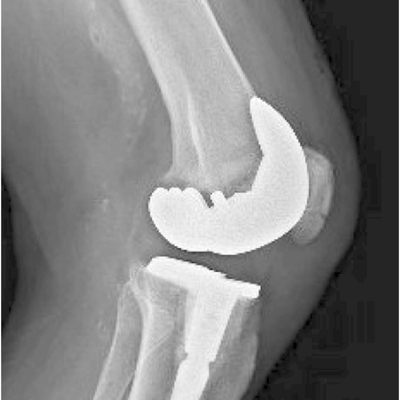

Click on an image below to view more info.